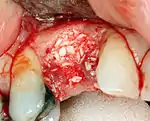

If bone width is inadequate it can be regrown using either artificial or cadaveric bone pieces to act as a scaffold for natural bone to grow around.

For an implant to osseointegrate, it needs to be surrounded by a healthy quantity of bone. In order for it to survive long-term, it needs to have a thick healthy soft tissue (gingiva) envelope around it. It is common for either the bone or soft tissue to be so deficient that the surgeon needs to reconstruct it either before or during implant placement.[32]:1084

Hard tissue (bone) reconstruction

Bone grafting is necessary when there is a lack of bone. Also, it helps to stabilize the implant by increasing survival of the implant and decreasing marginal bone level loss.[41] While there are always new implant types, such as short implants, and techniques to allow compromise, a general treatment goal is to have a minimum of 10 mm (0.39 in) in bone height, and 6 mm (0.24 in) in width. Alternatively, bone defects are graded from A to D (A=10+ mm of bone, B=7–9 mm, C=4–6 mm and D=0–3 mm) where an implant's likelihood of osseointegrating is related to the grade of bone.[42]:250

To achieve an adequate width and height of bone, various bone grafting techniques have been developed. The most frequently used is called guided bone graft augmentation where a defect is filled with either natural (harvested or autograft) bone or allograft (donor bone or synthetic bone substitute), covered with a semi-permeable membrane and allowed to heal. During the healing phase, natural bone replaces the graft forming a new bony base for the implant.[38]:223